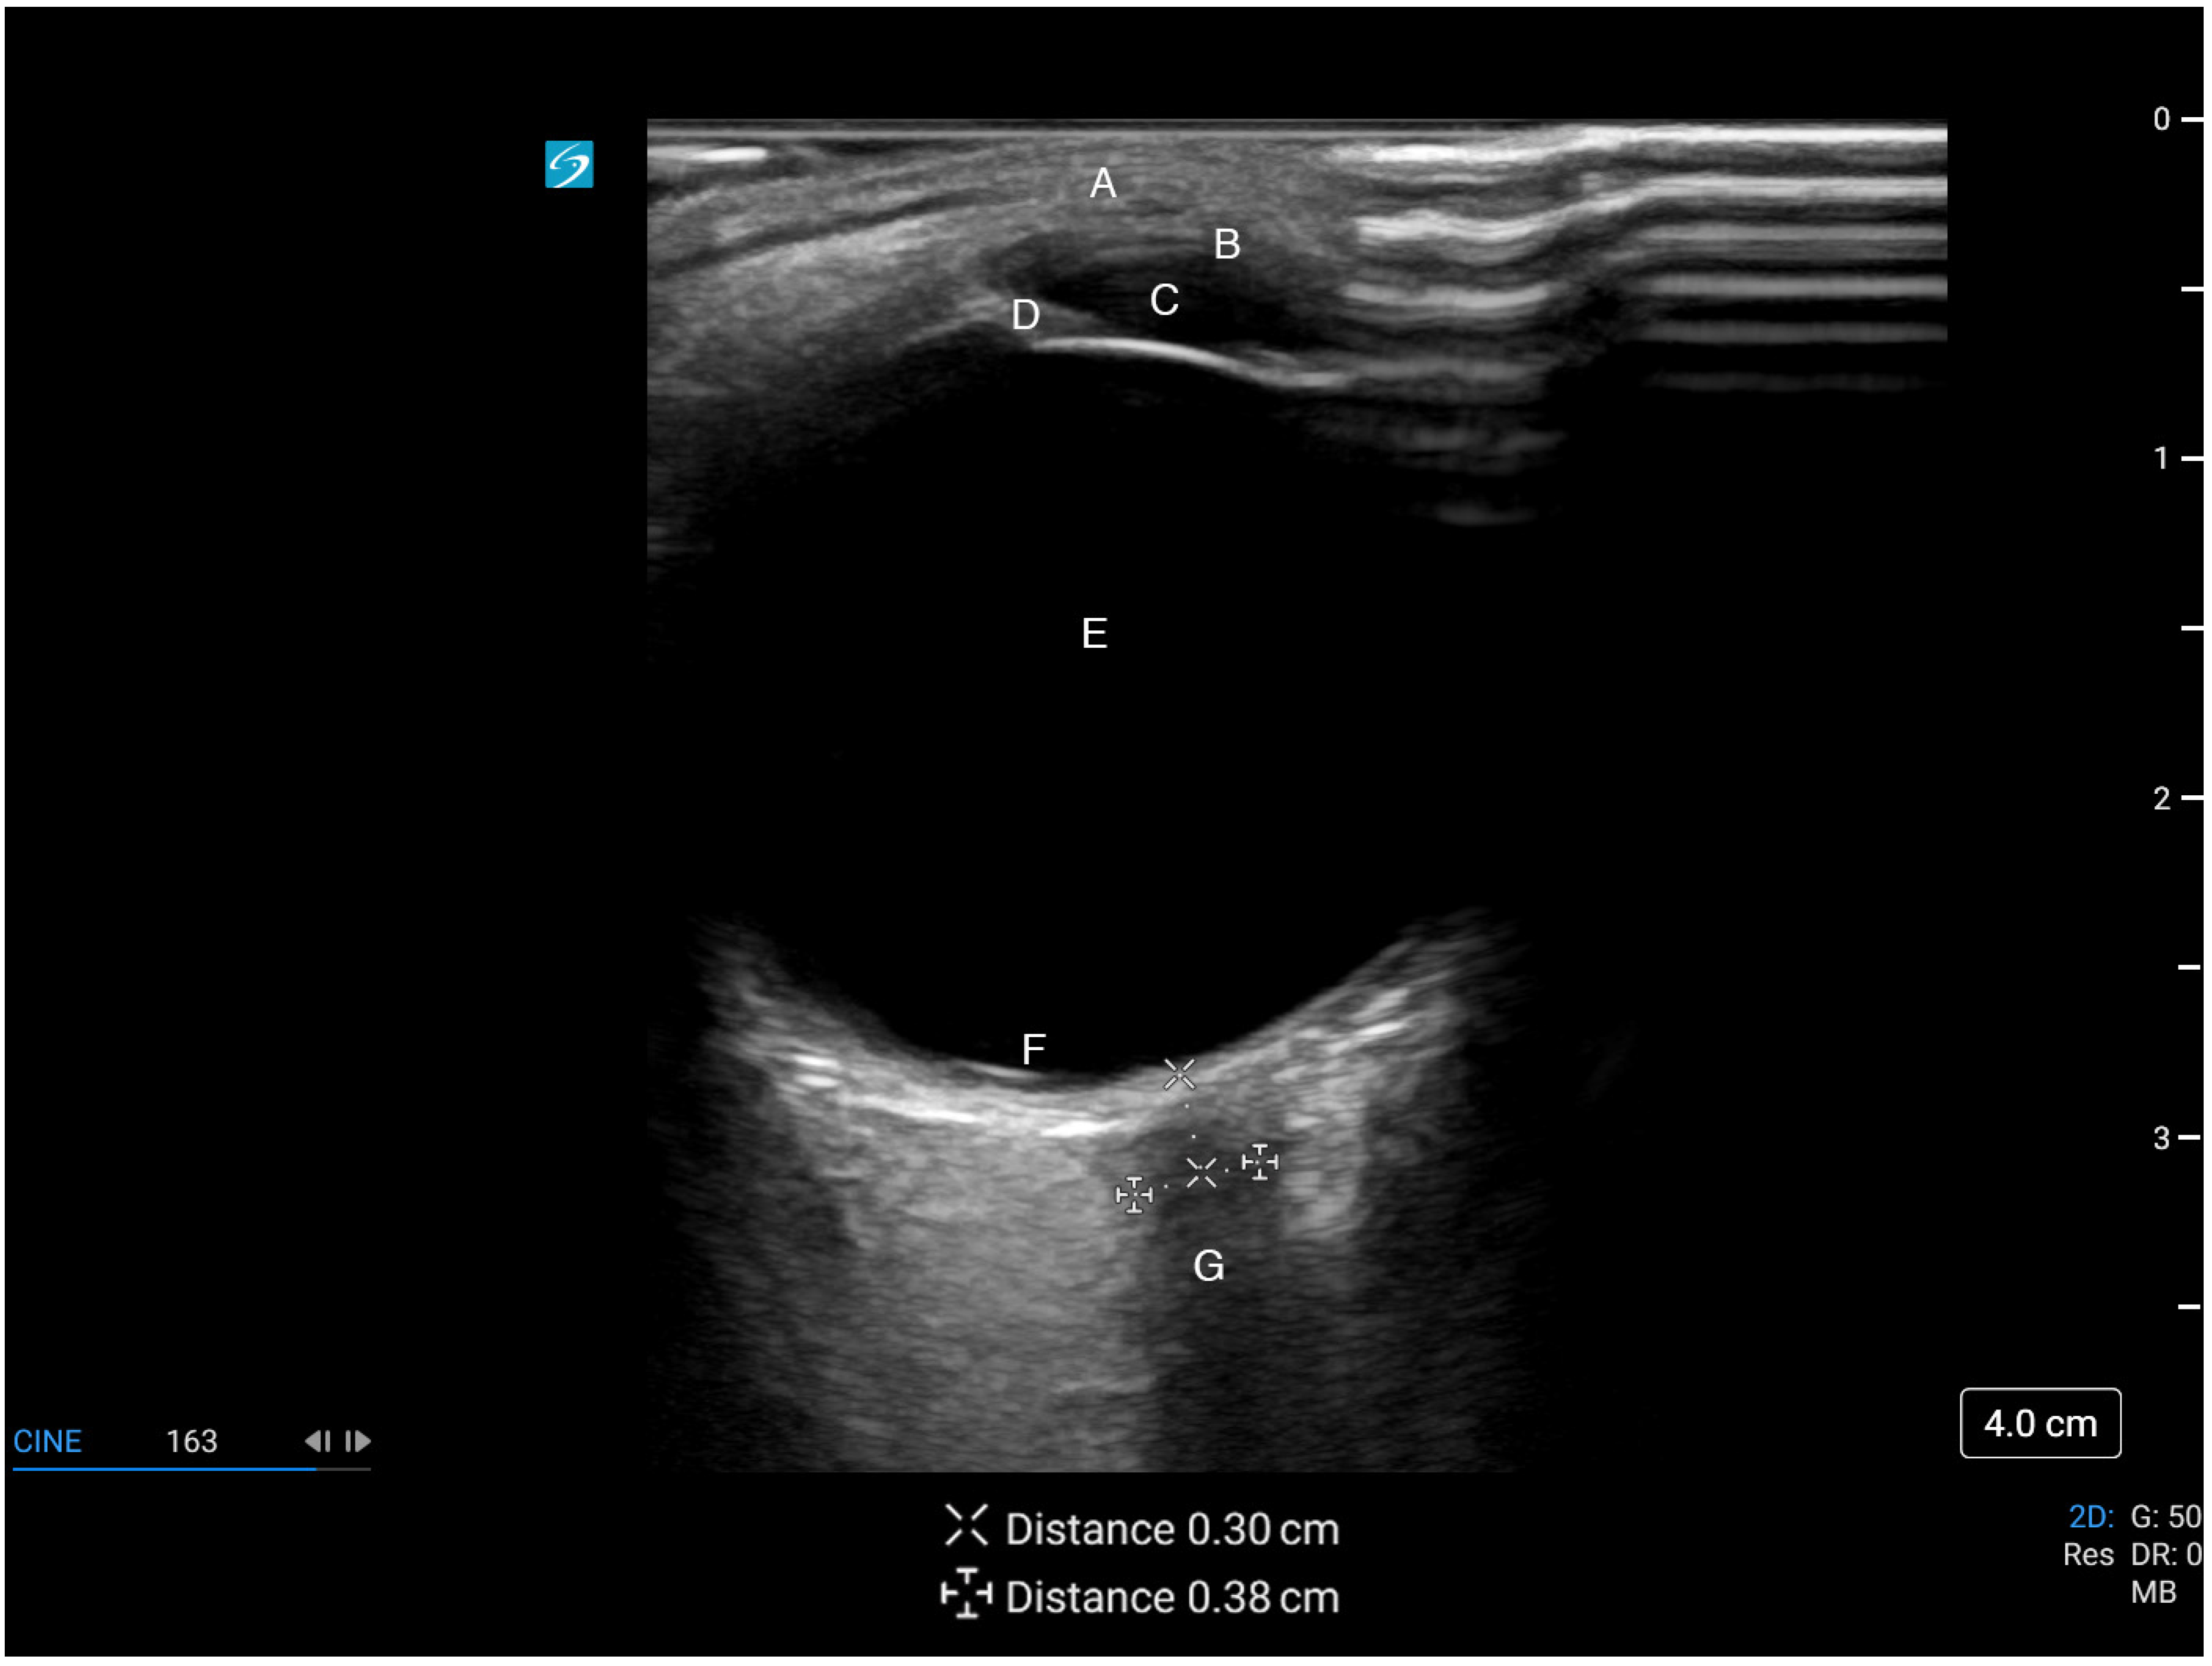

4.3. Scanning Technique and Sonographic Anatomy